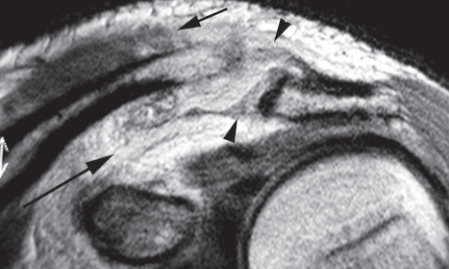

Coronal DP fast SE image shows complete tears of the acromioclavicular (arrowheads) and coracoclavicular (long arrow) ligaments and the trapezius insertion on the clavicle (short arrow).